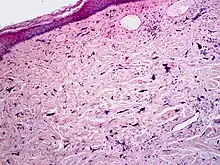

Pleomorphic fibroma